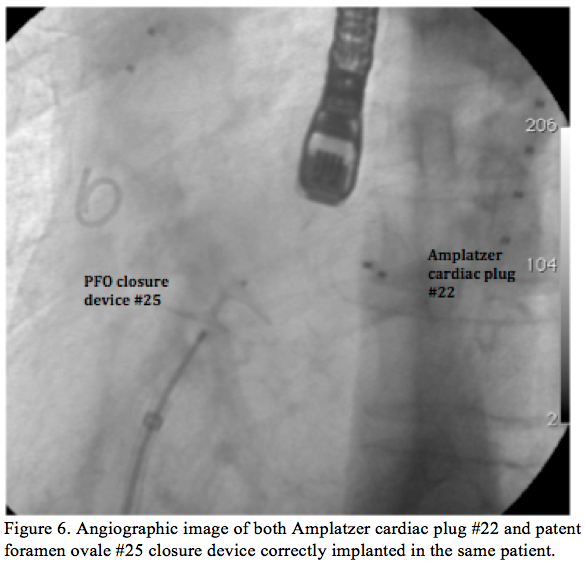

atrium, crossing uneventfully through the IVCF (Figure 4). The Amplatzer releasing system was delivered to the right atrium via the large, 90 cm, 10 Fr sheath positioned through the IVCF, avoiding further manipulation at the level of the IVCF (Figure 5). Standard left atrial appendage closure was performed with an Amplatzer Cardiac Plug (ACP) #22 device (AGA Medical Corporation). Using the same releasing system, a #25 Amplatzer device for PFO closure was successfully implanted (AGA Medical Corporation). Continuous monitoring of the procedure with transesophageal echocardiography was performed and the correct deployment of both devices was secured (Figure 6). Careful x-ray guided retrieval of the

trans-IVCF sheath was performed and final contrast media injection confirmed that no damage to the IVCF had occurred. After confirming the correct placement of both cardiac devices with echocardiography, the patient was discharged the following day.